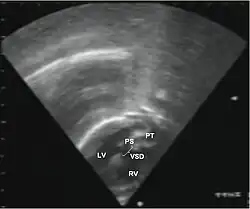

Additional images

Abbreviations: LV and RV=left and right ventricle, PT=pulmonary trunk, VSD=ventricular septal defect, PS=pulmonary stenosis.